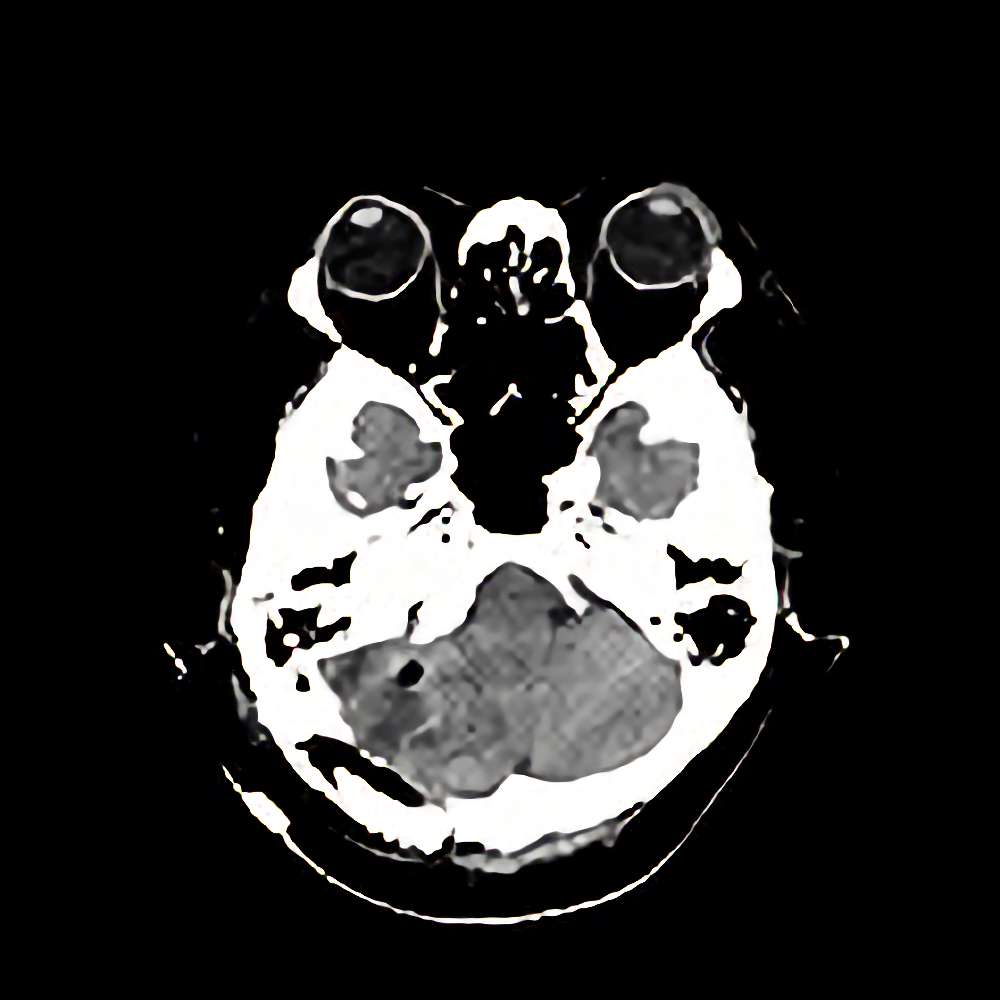

転移性脳腫瘍

断層撮影

手術前1

No.’12_131 手術前1